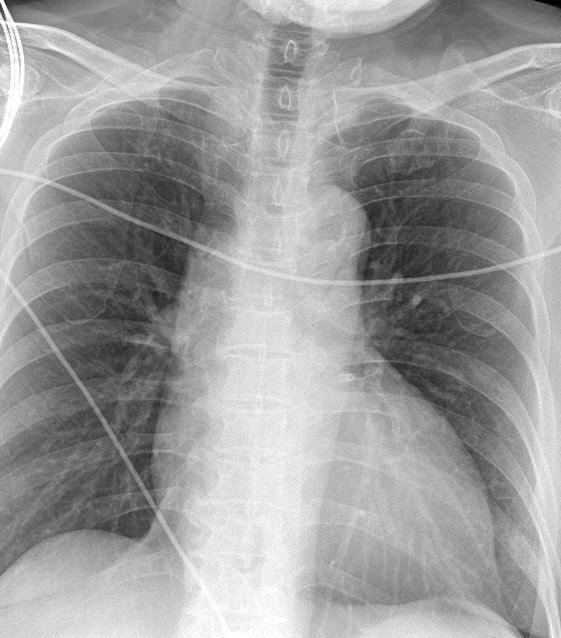

History Chief Complaint: 58 year old male presented with acute chest pain for 3 hours, radiating tothe left arm, associated with mild shortness of breath. No syncope orpalpitations.Past Medical History: Hypertension for 15 years, well-controlled withamlodipine and losartan.Dyslipidemia on rosuvastatin. Physical examination : no significant abnormal finding

Relevant Test Results Prior to Catheterization

Troponin T: 1.2 ng/mL (positive)